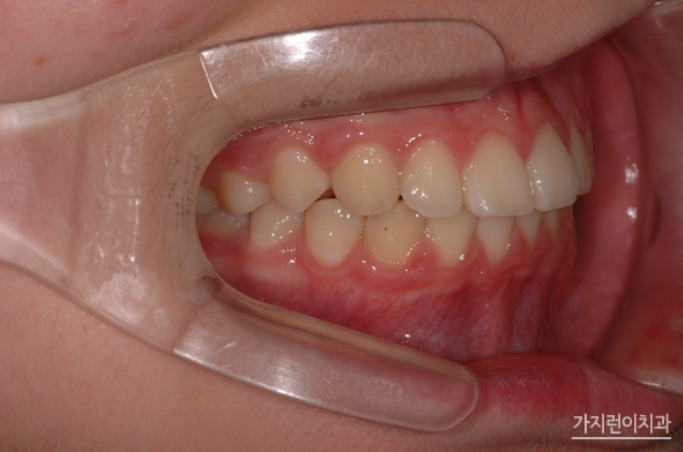

2년이 조금 넘는 시간 동안 치아교정을 진행한 환자분의 경우 전체적인 치열도 가지런해졌고, 무엇보다 과하게 튀어나왔던 앞니가 뒤로 들어가면서 정상적인 교합으로 돌아왔습니다. 앞으로 뻗은 채 누워 있는 형태를 보이던 앞니가 교정 후에는 정상적으로 세워져 있는 모습인데요. 무턱 증상을 보이던 부분이 개선되어 턱선이 되살아났다는 점을 주목해볼 수 있겠습니다.

만약 이 증상을 성인이 되어서 발견했으면 어땠을까요? 성장을 이용한 교정은 더 복잡한 교정, 복합적인 수술까지 가지 않로서 있는 골든타임 치료법인데요. 골격의 변화를 유도해 다방면으로 치아교정을 진행해볼 수 있으니 언제든 내원해 청소년 성장교정 상담을 받아보시기 바랍니다.